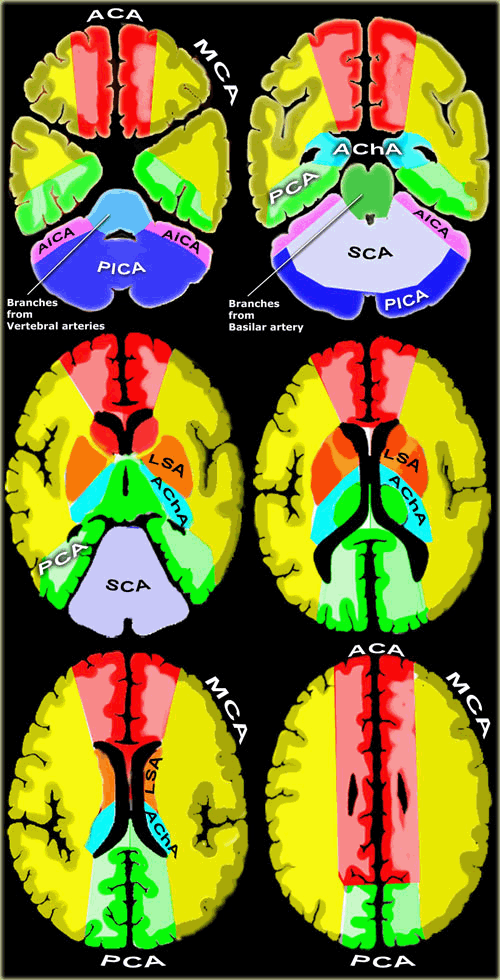

红色ACA:大脑前动脉

黄色MCA:大脑中动脉

绿色PCA:大脑后动脉

蓝色PICA:小脑后下动脉

紫色AICA:小脑前下动脉

灰色SCA:小脑上动脉

浅蓝Branches from Vertebral arteries:椎动脉分支

墨绿Branches from Basilar artery:基底动脉分支

天蓝ACHA:脉络膜前动脉

橙色LSA:豆纹动脉